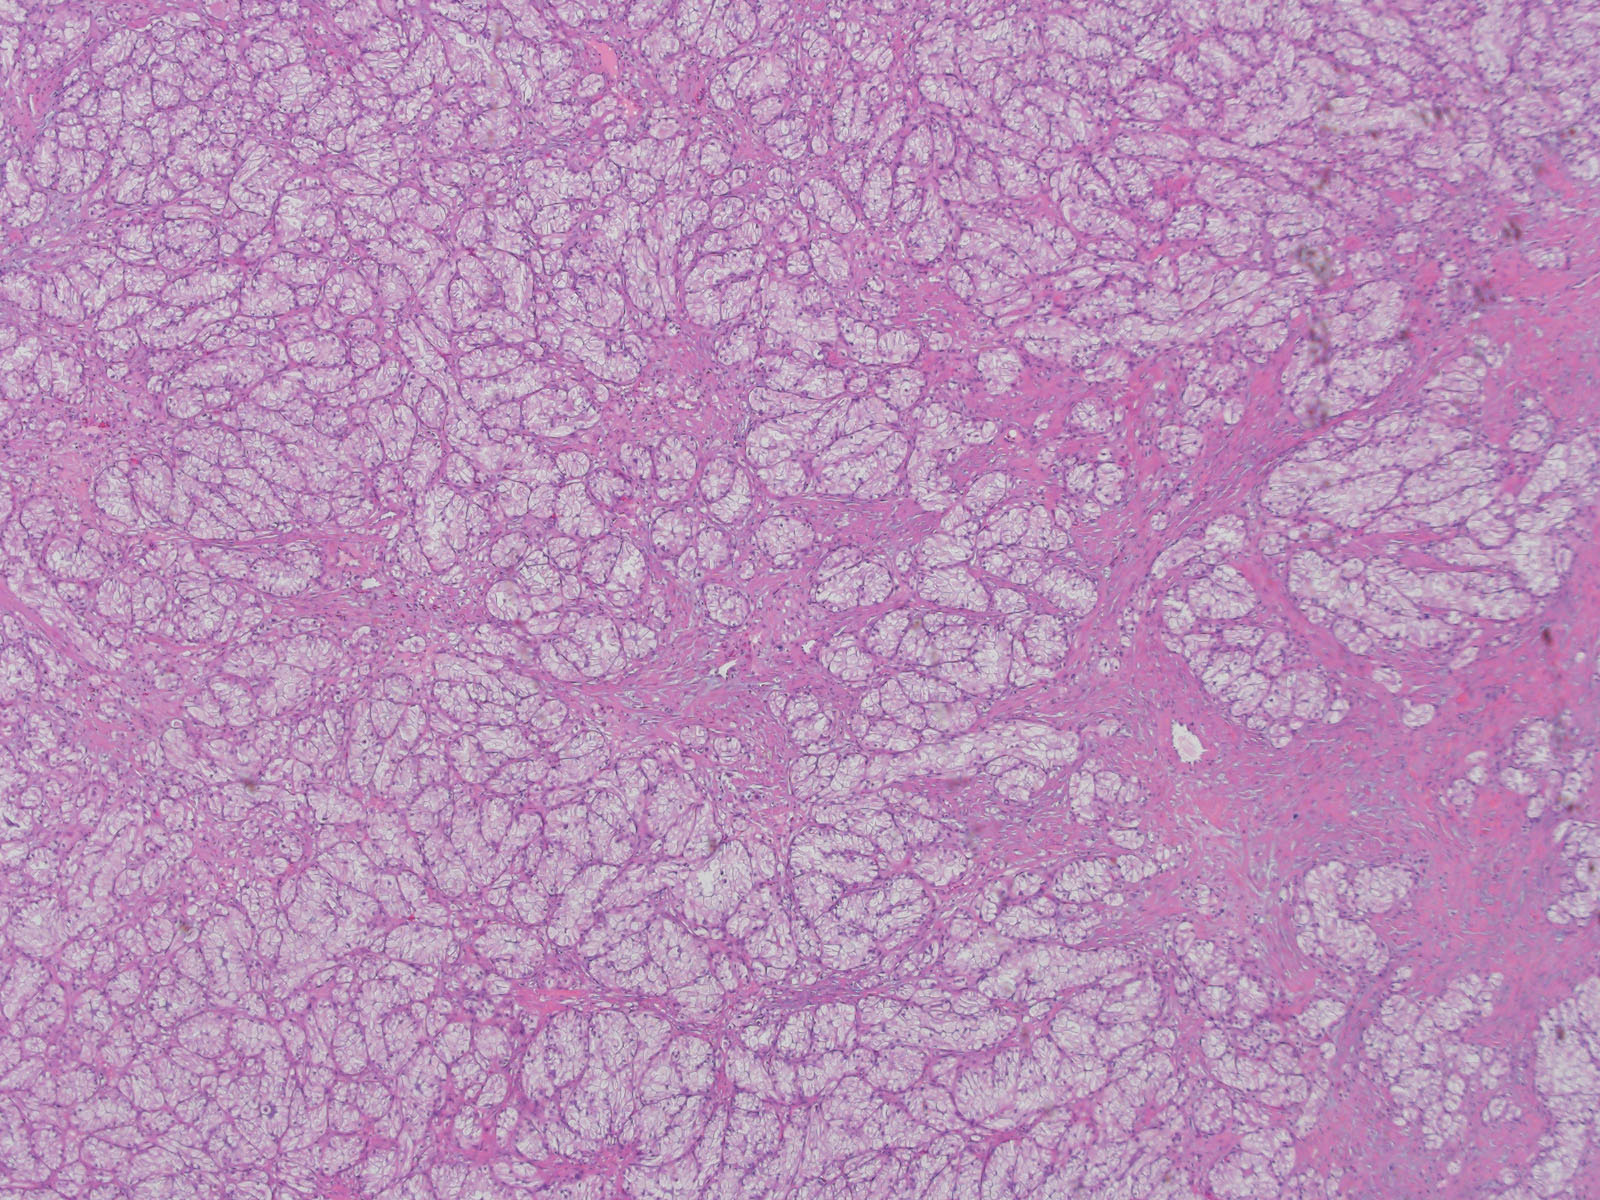

Classification of renal tumors

Case ID: 778